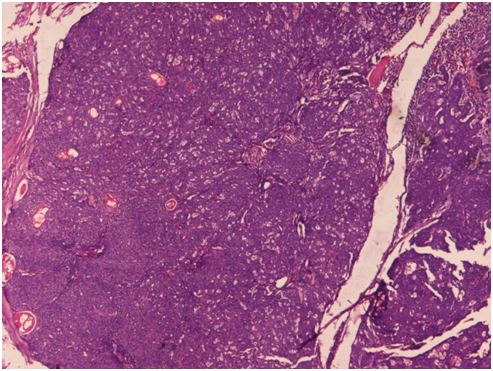

A 42year male presented to the skin outpatient department with chief complains of a single brownish painless lesion on his right cheek for the past one year. On examination, it was ulcerated and nodular, measuring 1.5×1.5cm in size. A clinical diagnosis of pigmented basal cell carcinoma (BCC) was made. The nodule was completely excised and the specimen was sent for histopathological diagnosis. On microscopic examination, section showed lobules and nests of tumor cells embedded in the dermis. Tumor cells were uniform with hyperchromatic nuclei and scant cytoplasm. Tumour islands also showed areas of retraction artifact as well as peripheral palisading of the nuclei on the periphery of the nests (Figure 1). However few aggregates of basaloid cells showed clusters of a sebaceous duct-like structure, containing keratinous debris. These clusters were mainly comprised of squamous cells with the peripheral part containing basaloid cells. Clusters also contained scattered vacuolated cells, with foamy cytoplasm (Figure 2). So a final diagnosis of Basal cell carcinoma (BCC) with sebaceous differentiation was given. The patient was completely asymptomatic after 1year of follow up period.

Figure 2 Section shows aggregates of basaloid cells with sebaceous duct-like structure, containing keratinous debris and scattered vacuolated cells, with foamy cytoplasm. Hematoxylin and Eosinx40X.